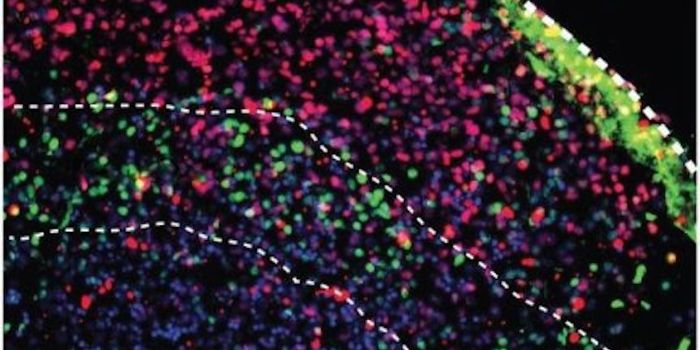

JUL 17, 2015NeuroscienceWhat causes autism? Is there something physical that accounts for behavioral differences?

Researchers have gr ... -